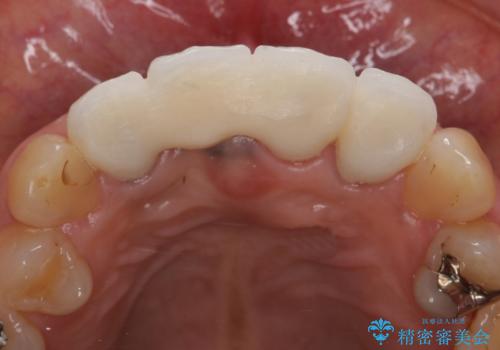

オールセラミッククラウン 折れてしまった前歯の治療

- 右上の前歯が折れてしまったので診て欲しいといらっしゃった方の症例です。

右上1番目の歯は保存不可能だったため抜歯し、ブリッジによる補綴を行いました。